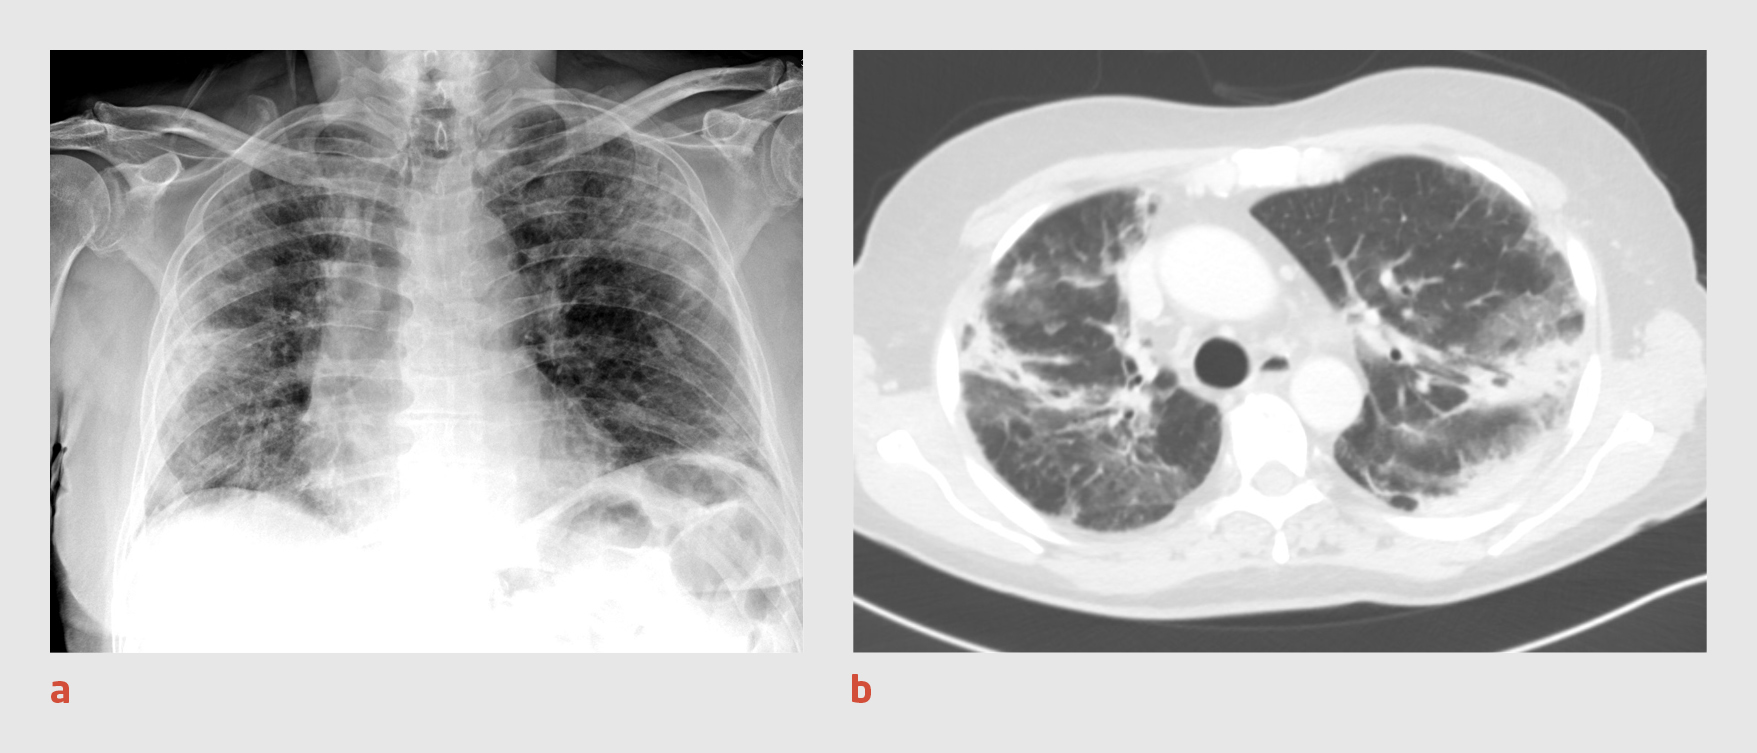

Patiënt B, een 82-jarige man die vanwege een lymfogeen gemetastaseerd urotheelcelcarcinoom wordt behandeld met pembrolizumab, bezoekt de Spoedeisende Hulp, omdat hij sinds 2 weken hoest en benauwd is. Hij heeft geen koorts gehad, is de laatste weken niet buitenshuis geweest en heeft geen contact gehad met covid-19-patiënten. Bij lichamelijk onderzoek zien we een matig zieke man met een zuurstofsaturatie van 92% zonder zuurstofsuppletie en een ademhalingsfrequentie van 18/min. Bij auscultatie van de longen horen we beiderzijds basaal crepitaties. Bloedonderzoek geeft de volgende uitslagen: lymfocytengetal: 1,08 x 109/l; CRP: 60 mg/l; en LDH: 326 U/l. De thoraxfoto toont een ‘moppig’ beeld met perifeer gelegen consolidaties in beide longen (figuur 2a). Patiënt wordt opgenomen in strikte isolatie onder de werkdiagnose ‘covid-19’.

Figuur 2

Thoraxfoto en CT-thorax van patiënt B

Figuur 2 | Thoraxfoto en CT-thorax van patiënt B

(a) Thoraxfoto van een 82-jarige man waarop een ‘moppig’ beeld te zien is met perifeer gelegen consolidaties in beide longen. (b) Op de CT-scan van de thorax zijn in beide longen – met name in de bovenvelden – matglasafwijkingen en grillige consolidaties zichtbaar, overeenkomstig een CO-RADS-score van 4.

Er wordt een PCR-test verricht op SARS-CoV-2 in materiaal uit de nasofarynx en patiënt wordt intraveneus behandeld met ceftriaxon 2 g 1 dd. De volgende dag blijkt de uitslag van de PCR-test negatief te zijn. Omdat wij op basis van het klinische beeld nog steeds een sterk vermoeden van covid-19 hebben, wordt CT-onderzoek van de thorax verricht. Op de CT-scan worden in beide longen – met name in de bovenvelden – matglasafwijkingen en grillige consolidaties gezien (CO-RADS-score 4) (figuur 2b). De isolatiemaatregelen blijven gehandhaafd en er wordt nog tweemaal een PCR-test verricht, waarvan de uitslag beide keren negatief is.

Na overleg met de behandelend oncoloog concluderen we dat het klinische beeld en de afwijkingen op de CT-scan goed passen bij pneumonitis onder immunotherapie. Patiënt wordt behandeld met prednisolon 1 mg/kg per dag, waarna hij binnen enkele dagen opknapt en naar huis kan worden ontslagen. Patiënt wordt poliklinisch gevolgd, waarbij de thoraxfoto’s telkens een verbetering van het longbeeld laten zien. Op dit moment voelt patiënt zich goed en wordt de behandeling met prednisolon afgebouwd.